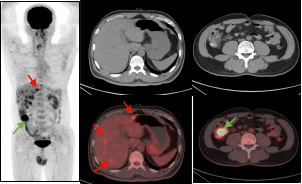

男,56岁,CEA: 40.5ng/ml,图A:肝脏多发转移瘤(红色箭头),图B:显示结肠肝曲高代谢肿块(绿色箭头),经肠镜证实为结肠腺癌。

右肺下叶肺癌伴阻塞性肺炎患者,CT难以精准指导穿刺,而PET/CT可准确区分肿瘤组织及炎性病变。绿色箭头示炎性组织,红色箭头示高代谢区域为肿瘤组织。